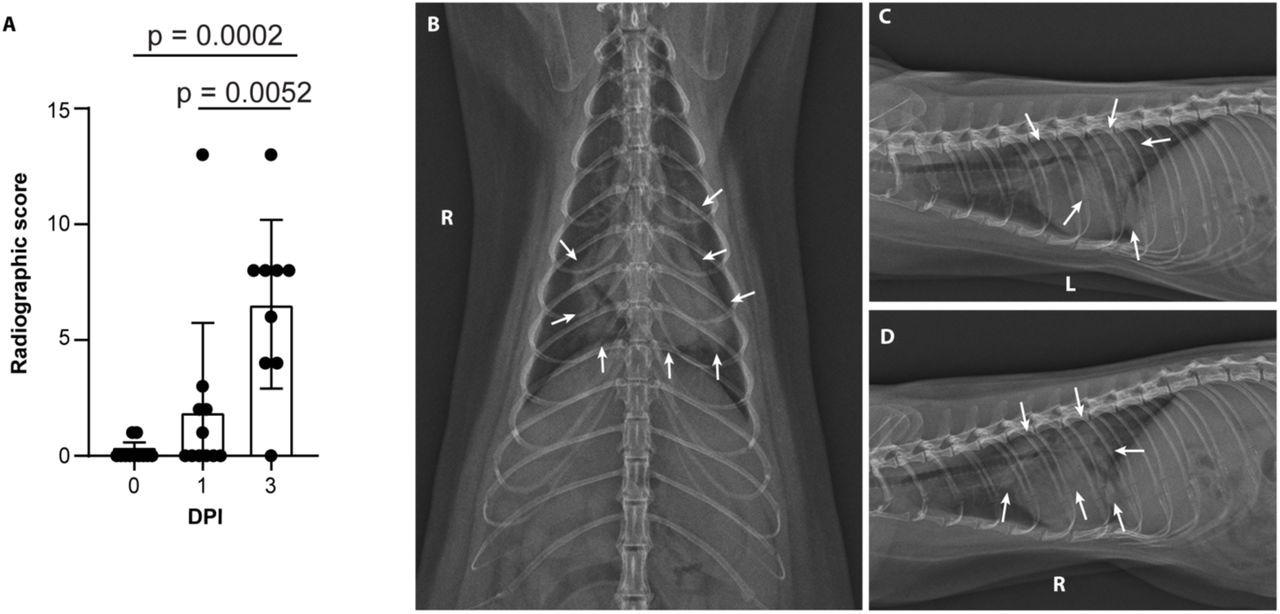

Minks develop severe COVID-19 infection 2 days after exposureSevere radiological changes after infection with SARS-CoV-2. (A) Compiled radiographic scores. Bar graph depicts the mean with standard deviation and individuals, ordinary one-way ANOVA with Tukey’s multiple comparisons test. Radiographs demonstrate multifocal pulmonary infiltrates, most severe in the left and right caudal lung lobes depicted in the (B) dorsoventral radiograph (C) left lateral and (D) right lateral radiograph on the evening of 2 days post-inoculation (DPI). Arrows depict grade 4 pulmonary disease in the left and right caudal lung lobes with grade 3 pulmonary disease in the right middle lung lobe and cranial subsegment of the left cranial lung lobe.

Minks developed progressive pulmonary infiltrates consistent with viral pneumonia from ARDS on the first and third day after exposure.